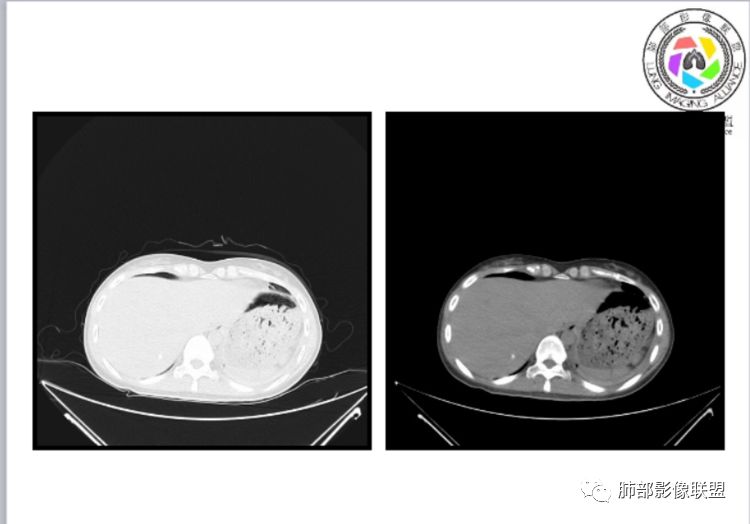

小微:右肺下叶斑片状密度增高影,抗炎治疗6天后复查,双肺下叶出现斑片状密度增高影,排除炎性病变,D2聚体特别高,考虑肺栓塞,肺梗死,建议增强扫描。王开金江津中心医院呼吸科:@岳微-辽宁PLA234医院放射科?支持,患者年轻女性,胸痛主诉,使用雌激素,高危人群,心率快,d二聚体升高,右下叶斑片加肺动脉明显增宽,抗感染无效,要考虑PTE,建议肺动脉ctpa。傅昌瑜:19岁,女性,右侧胸痛2天,发热以中度热为主,D—二聚体升高,肺动脉主干增宽,病灶位于胸膜下,抗感染后增多,近来有服用炔雌醇环丙孕酮片2周期史,诊断:肺栓塞,下一步完善肺CTPA检查。阿仙奴:青年女性,急性起病,胸痛入院,月经不调史,目前服用孕酮片。流感抗体阳性,d二聚体升高,无低氧血症。右肺下叶基底段胸膜下磨玻璃样改变,肺动脉增宽,治疗过程出现发热,复查左下叶胸膜下新发病灶。考虑:肺栓塞(服用孕酮相关)?奔跑的37°Doctor(陆喜红 ) :年轻女性,胸痛 急性病程,有服用雌激素避孕药史(是否有血液循环的改变,高凝状态),实验室D二聚体很高(也是提示血液高凝状态) ,第一次CT,右下肺胸膜下斑片状密度增高模糊影,肺动脉形态密度未见明显异常,抗炎后复查,肺动脉干及其分支,感觉增粗了一点,局部形态有点饱满,双下肺胸膜下片状影增多,锁定肺动脉栓塞应该不会错,建议CTA检查飞鹰行动:青年人,女性,右肺下叶斑片状密度增高影,抗炎治疗6天后复查无好转,,双肺下叶出现斑片磨玻璃影,主肺动脉增粗,结合患者服用的药物和D2聚体特别高,考虑肺栓塞,建议CTA。李:口服避孕药,有危险因素,肺动脉较主动脉增宽,D二聚体增高,胸膜下片状影,考虑肺栓塞;@晨义工张帅,医附属潞河医院呼吸?是否痰中带血很关键,不知有没有张帅:患者入院后第七天出现痰中带血风之子:病程中有发热,D—二聚体升高,肺动脉主干增宽,病灶分布于胸膜下,抗感染后增多,结合服药史诊断:肺栓塞,建议CTPA检查。不支持的地方是没有低氧血症,不明白为什么第二次复查ct双侧乳腺不对称,按理乳腺炎多见于哺乳期张帅:大家方向都在考虑肺栓塞:我提问两个问题:1 周围毛玻璃怎么回事?2左下肺小叶间隔增宽怎么回事?笨丫头:周围的磨玻璃应该考虑是肺梗死后出血渗出,同时合并机化性炎症小叶间隔增宽,我考虑应该是梗死后炎性渗出wonderful:我不支持肺栓塞 不能解释发热原因

水晶石头:患者青少年女性,右侧胸痛2天就诊。有咳嗽,无痰。初次胸部CT:右下肺片状模糊影。入院后经头孢美唑、莫西沙星抗感染治疗6天后复查胸部CT:右下肺病灶加重,且左下肺出现类似病灶。结合其气管镜气道无异常,病程中有发热,D—二聚体升高,近来因月经不调有服用炔雌醇环丙孕酮片史。诊断考虑良性非感染性。肺栓塞可能性大,鉴别血管炎及子宫内膜肺异位可能。流心明智:女性,19岁,右侧胸痛2天,中度热为主,D—二聚体升高,影像:肺动脉主干小于29mm,病灶位于右下肺胸膜下,斑片影,胸膜侧宽基底,抗感染后增多,左下肺亦出現类似病灶,似有反晕、融冰征。近来有服用炔雌醇环丙孕酮片2周病史,考虑诊断:肺栓塞。具体性质及发病机制有待进一步检查。尘缘:@吴永丽 灌云县医院 呼吸?应该是的,左下肺的磨玻璃影像后面也支持有出血改变所以可能就是一个子宫内膜异位出血合并感染

1、一个或多个胸膜下斑片高密度影(梗死、出血、肺不张、肺水肿、炎性渗出),典型为胸膜下楔形影 ,尖端指向肺门

3、肺血减少

3.影像:病变胸膜下多发斑片影,提示与血管有关,早期病变为渗出,应该是早期的炎性渗出,病灶抗感染治疗后实变区增多、变大,临床症状又出现咯血,CT上应该合并了肺泡出血、梗死、肺不张及肺水肿;